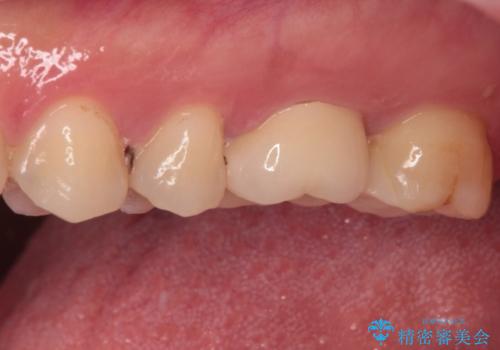

強い咬合力を負担する第一大臼歯であるため、根管治療後は速やかにオールセラミッククラウンにて補綴治療を行うこととしました。